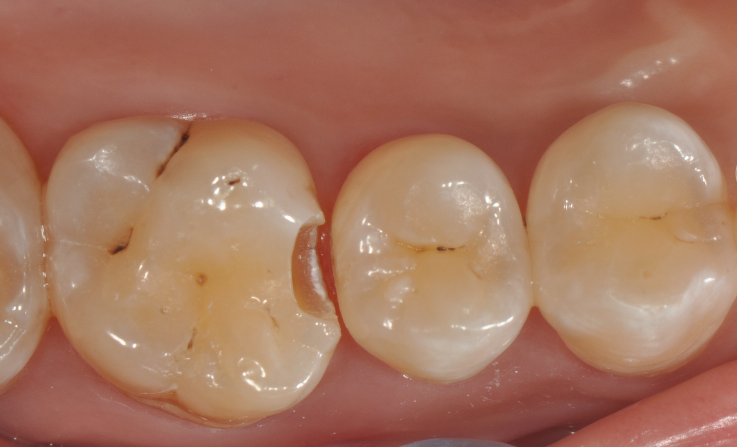

牙医-马小寒【实操病例】

右上6号牙位的近中,可见隐约龋坏

◆去腐完成之后

在以树脂充填为前提的案例中,无需过度制作颌面的鸠尾固位型,橡皮障下隔湿,是临床粘结操作技术成功的重要保障。酸蚀剂在使用的时候,需要尽量避免对邻牙的伤害

◆该成形片能更好的将龈缘区域的边缘封闭性做的更好。尤其是在邻面区域,涂布第六代粘结剂,固化粘结剂之后,配合高填料流体树脂和后牙专用树脂进行该洞形的充填。

◆术后即刻照,如果邻面边缘出现悬突,可以使用12#手术刀去除,再配合抛光条抛光

◆术后撤离橡皮障后口内照片,术后1周复查,我们修正了边缘嵴的斜度及邻面轴线上的多余材料;复查是很重要的,能够发现第一次操作的时候遗留的不足,并且再次修正,保障了充填体的寿命。该案例也得益于改善了的成形片,修正了以往的成形片邻面龈缘区域材料残留形成过多的悬突材料,避免了术后龈乳头炎的发生!